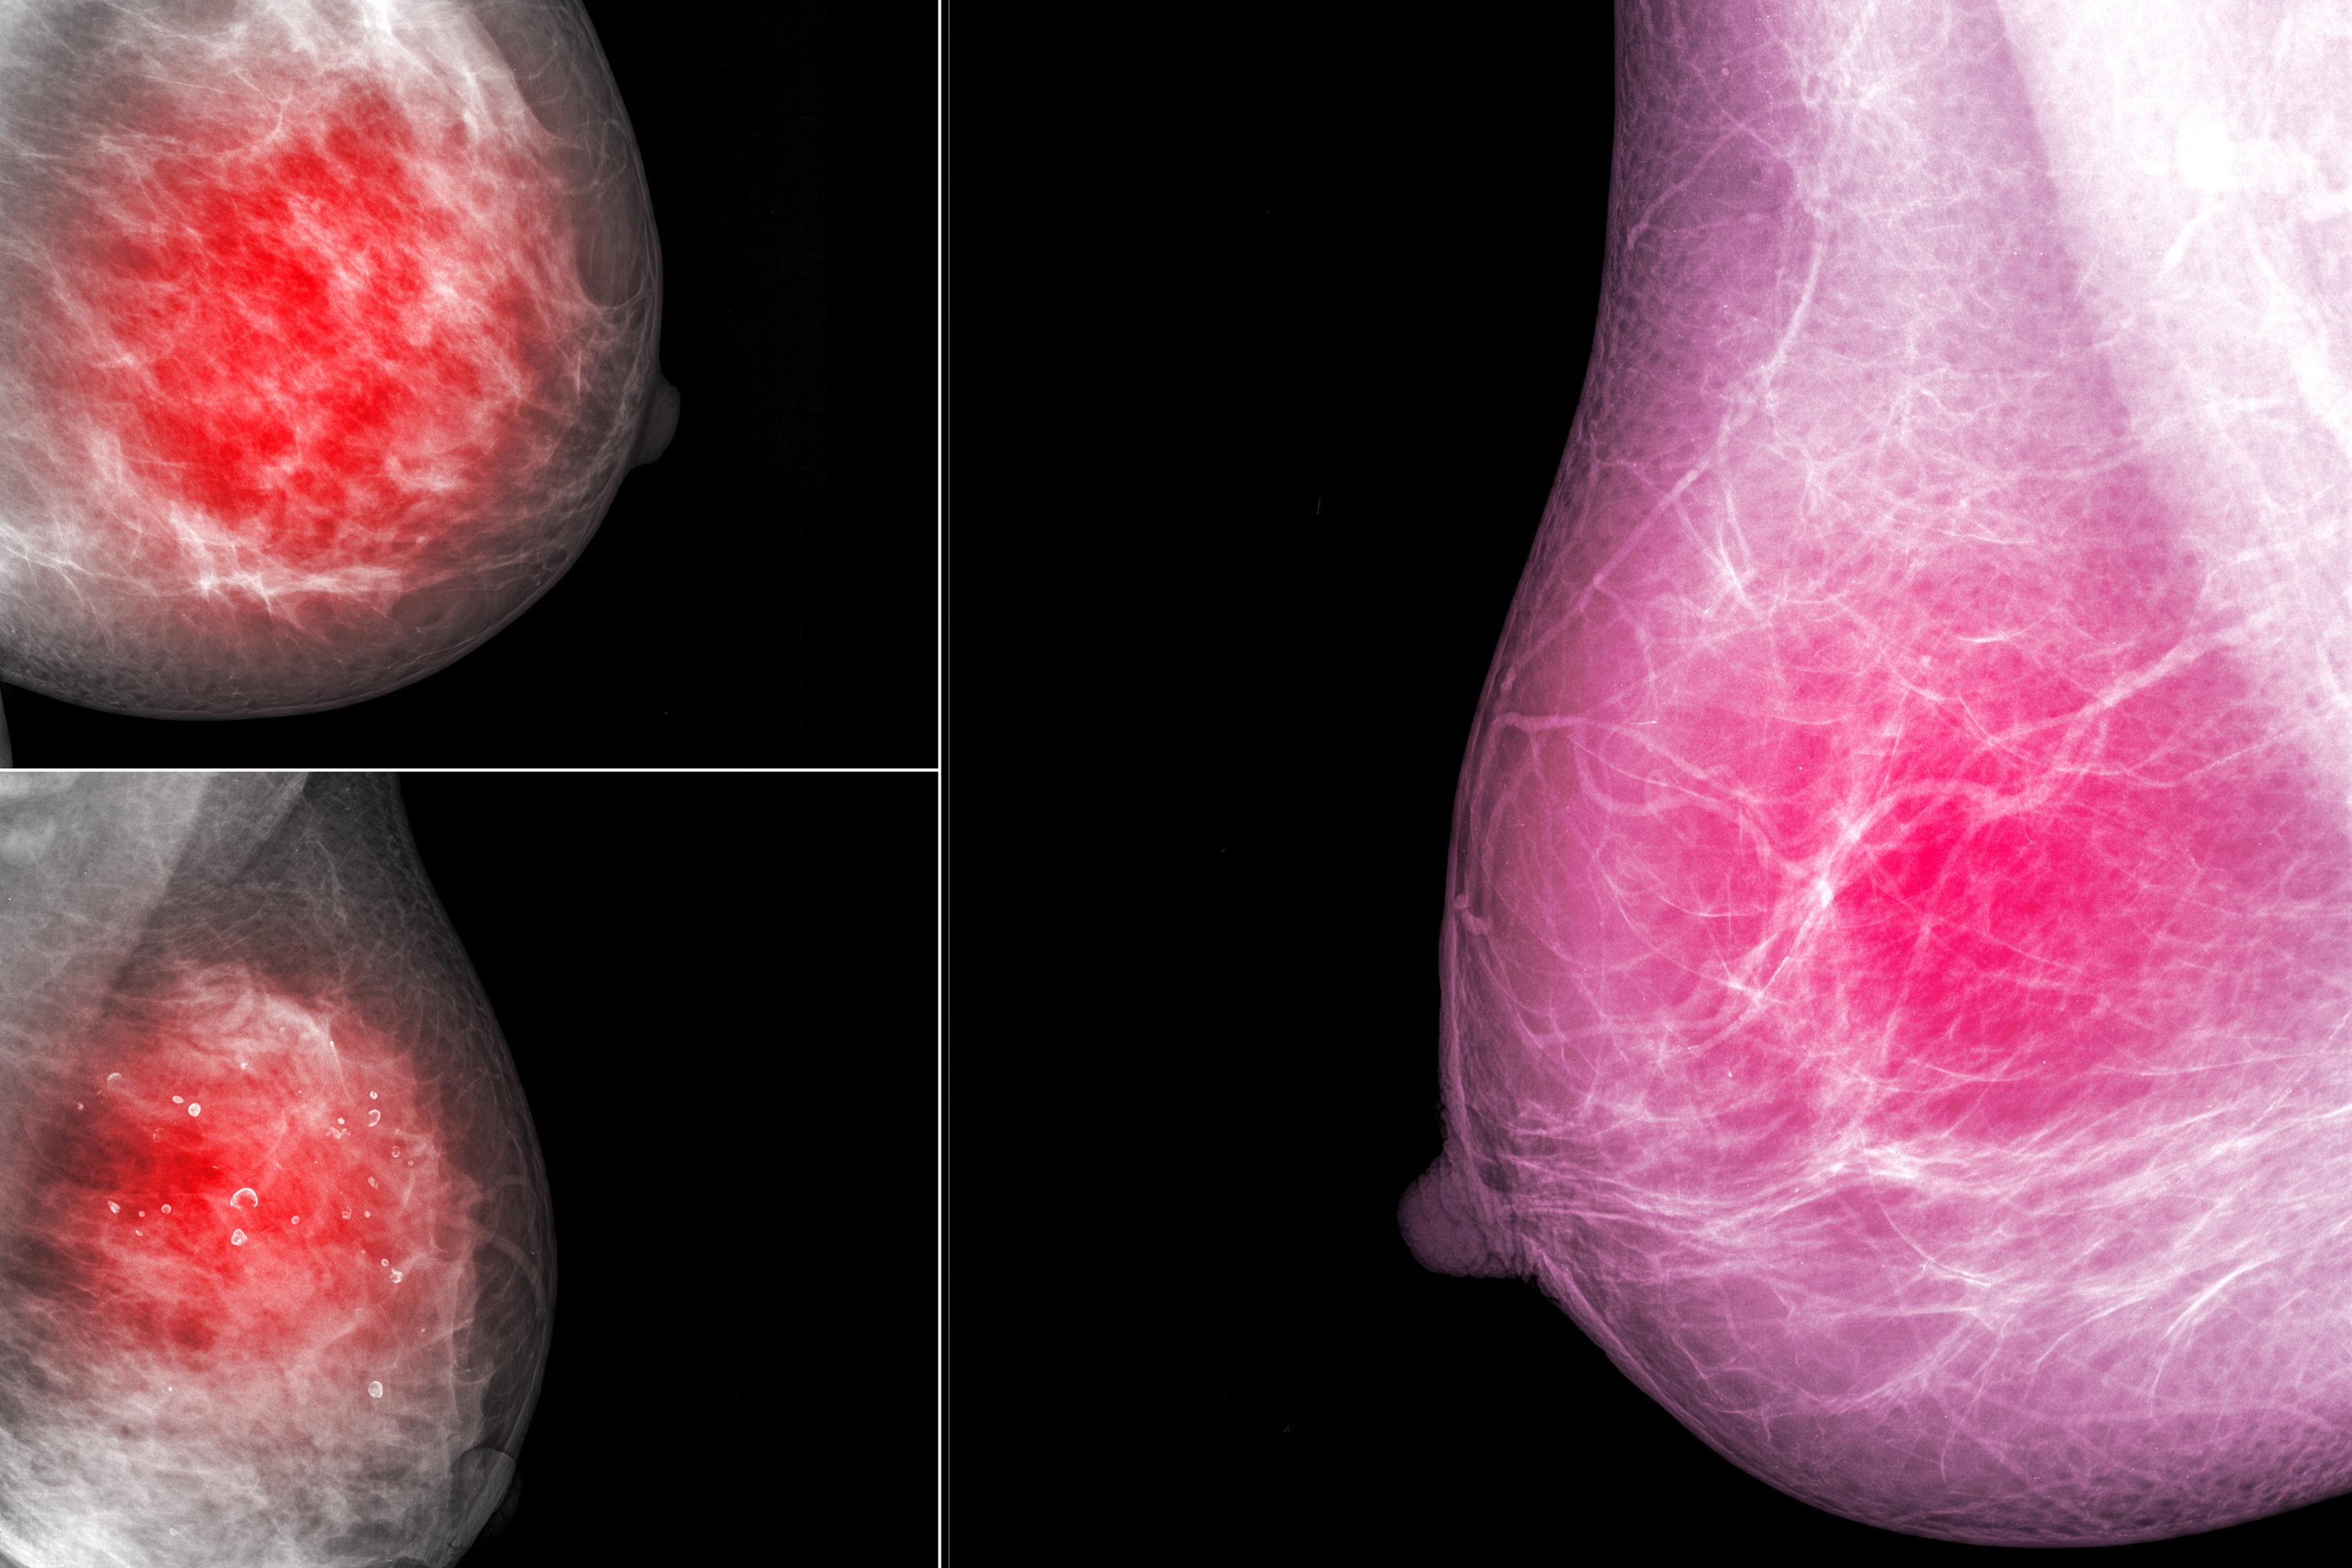

Breast Cancer Exam-Room Anatomy Posters | ClinicalPosters

Breast Cancer Exam-Room Anatomy Posters | ClinicalPosters

Breast Cancer Exam-Room Anatomy Posters | ClinicalPosters,

Breast Cancer Exam-Room Anatomy Posters | ClinicalPosters, T-DXd Now Preferred for All Patients With HER2+ Metastatic,